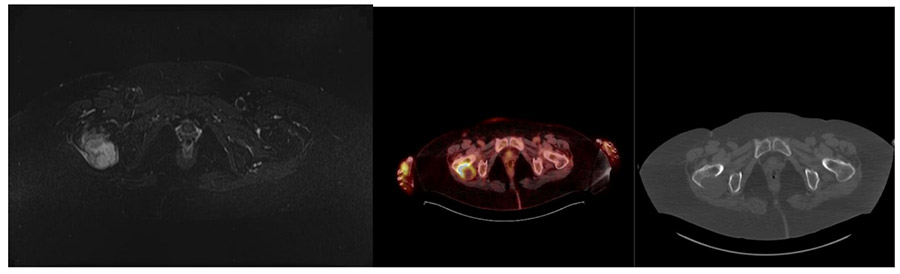

Before the surgery: MRI shows tumor tissue extending beyond the bone, causing damage to the posterior aspect of the right hip bone, while PET-CT shows involvement and bone destruction in the metastatic area.